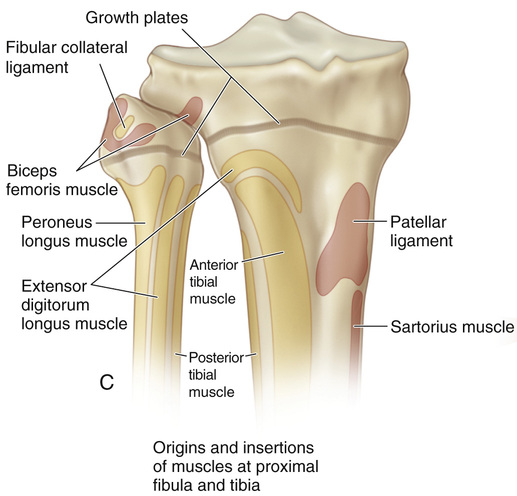

Pin by Rick Steele on Анат | Anatomy bones, Skeletal system anatomy …

Pin on Knee

54 Epiphysiodesis of the Proximal Tibia and Fibula (the Green …